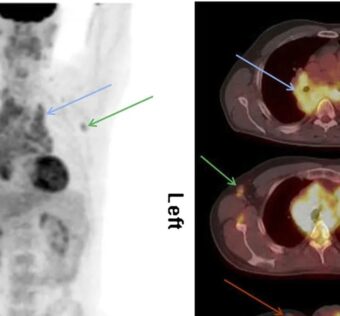

Cutting-Edge PET Tracer Revolutionizes Early Detection of Inflammatory ArthritisDistilINFO Hospital IT - (Monday February 12, 2024) - Daily Reads/ DistilINFO Hospital IT | |

![]() | Experience the revolutionary potential of a cutting-edge PET tracer for early arthritis detection. Inflammatory arthritis, particularly rheumatoid arthritis, poses significant challenges due to its insidious onset and devastating consequences. This innovative PET imaging technique,... #CuttingEdgePETTracerRevolutionizesEarlyDetectionofInflammatoryArthritisA recent blog post discusses how a cutting-edge PET tracer is revolutionizing the early detection of inflammatory arthritis. The post highlights the importance of early diagnosis and the limitations of current diagnostic methods.#The Need for Early DetectionThe blog post emphasizes the need for early detection of inflammatory arthritis, as early intervention can significantly improve patient outcomes. It explains that traditional diagnostic methods, such as X-rays and blood tests, often fail to detect the disease in its early stages.#Introduction to the Cutting-Edge PET TracerThe blog post introduces a new PET tracer that has shown promising results in detecting inflammatory arthritis at an early stage. It explains that PET imaging As a healthcare IT expert, write a 50-80 extractive summarization summary for social media platforms, that is focused, accurate, and strictly reflects the content based on a blog post from the given URL. The summary should include all headings from the blog post, with inline hashtags for each heading. When including the inline hashtags, use specific hashtags related to the headings rather than generic healthcare or technology hashtags. If the headings in the blog post are too long or unclear, feel free to rephrase them into shorter, clearer versions that still convey the main idea. The target audience is other healthcare IT professionals.Following is the title and url. Cutting-Edge PET Tracer Revolutionizes Early Detection of Inflammatory Arthritis https://distilinfo.com/hospitalit/2024/02/12/cutting-edge-pet-tracer-revolutionizes-early-detection-of-inflammatory-arthritis/ { "id": "chatcmpl-8rOdvqfgiJgd2EtQSpkPxMLKCOq9L", "object": "chat.completion", "created": 1707736803, "model": "gpt-3.5-turbo-0613", "choices": [ { "index": 0, "message": { "role": "assistant", "content": "#CuttingEdgePETTracerRevolutionizesEarlyDetectionofInflammatoryArthritisnnA recent blog post discusses how a cutting-edge PET tracer is revolutionizing the early detection of inflammatory arthritis. The post highlights the importance of early diagnosis and the limitations of current diagnostic methods. nn#The Need for Early DetectionnnThe blog post emphasizes the need for early detection of inflammatory arthritis, as early intervention can significantly improve patient outcomes. It explains that traditional diagnostic methods, such as X-rays and blood tests, often fail to detect the disease in its early stages. nn#Introduction to the Cutting-Edge PET TracernnThe blog post introduces a new PET tracer that has shown promising results in detecting inflammatory arthritis at an early stage. It explains that PET imaging" }, "logprobs": null, "finish_reason": "length" } ], "usage": { "prompt_tokens": 187, "completion_tokens": 150, "total_tokens": 337 }, "system_fingerprint": null } Prompt Tokens - 187 |